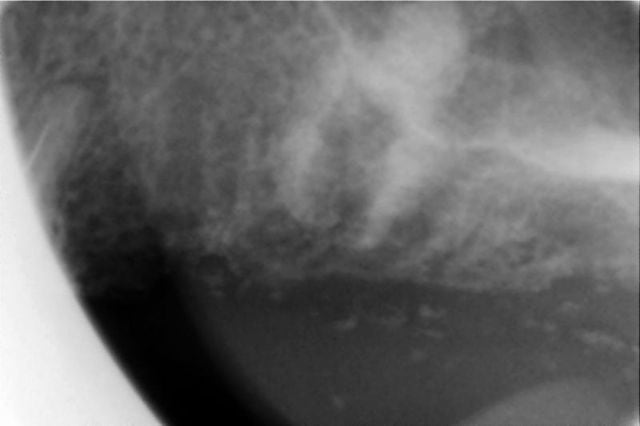

bon, je vous livre à chaud mes impressions positives et négatives:

ci joint 6 photos avant pendant et après,

je n'ai donc pas aplani comme conseillé,

j'ai passé le forêt pilote puis les ostéotomes 2.7 et 3.2,

le cliché de contrôle avant pose de l'implant montre bien le dôme du matériau de comblement, jusque là tout allait bien et je pensais que le plus dur était fait,

c'est après que j'ai été ennuyé:

j'ai commencé à visser à la main le WP de 5 mm

et j'ai rencontré une résistance quand il était à ras de la corticale V alors que du côté palatin j'avais une déhiscence de 2 mm ( normal je n'avais pas aplani)

j'ai eu l'impression qu'il perdait en stabilité et tournait sur lui même, curieux pour un os tendre?

la situation ne me plaisait pas et je l'ai dévissé, puis

j'ai élargi un peu au counterbore, et j'ai revissé,

aucune amélioration donc le problème était soit à l'apex de l'implant( perforation trop étroite pour le passage d'un implant cylindrique), ou alors le long des parois, auquel cas j'aurais dû passer un ostéotome de 3.7, ou même 4.2 ce qui me paraissait un peu trop pour un WP sur un os peu dense,

j'ai quand même réussi en changeant un peu l'inclinaison à le bloquer manuellement à 40 Ncm et sans déhiscence

qu'est-ce qui a pu résister au vissage de l'implant:

1- un os trop dense donc dernier ostéotome trop étroit?

2- un orifice de perforation de la corticale sinusienne trop étroit de 3.2 mm pour un implant de 5 mm non conique ?

3- autre chose que je n'ai pas vu ?

en tout cas, sur les clichés, le beau dôme que l'on voit avant implantation a disparu après pose de l'implant; où est le matériau?